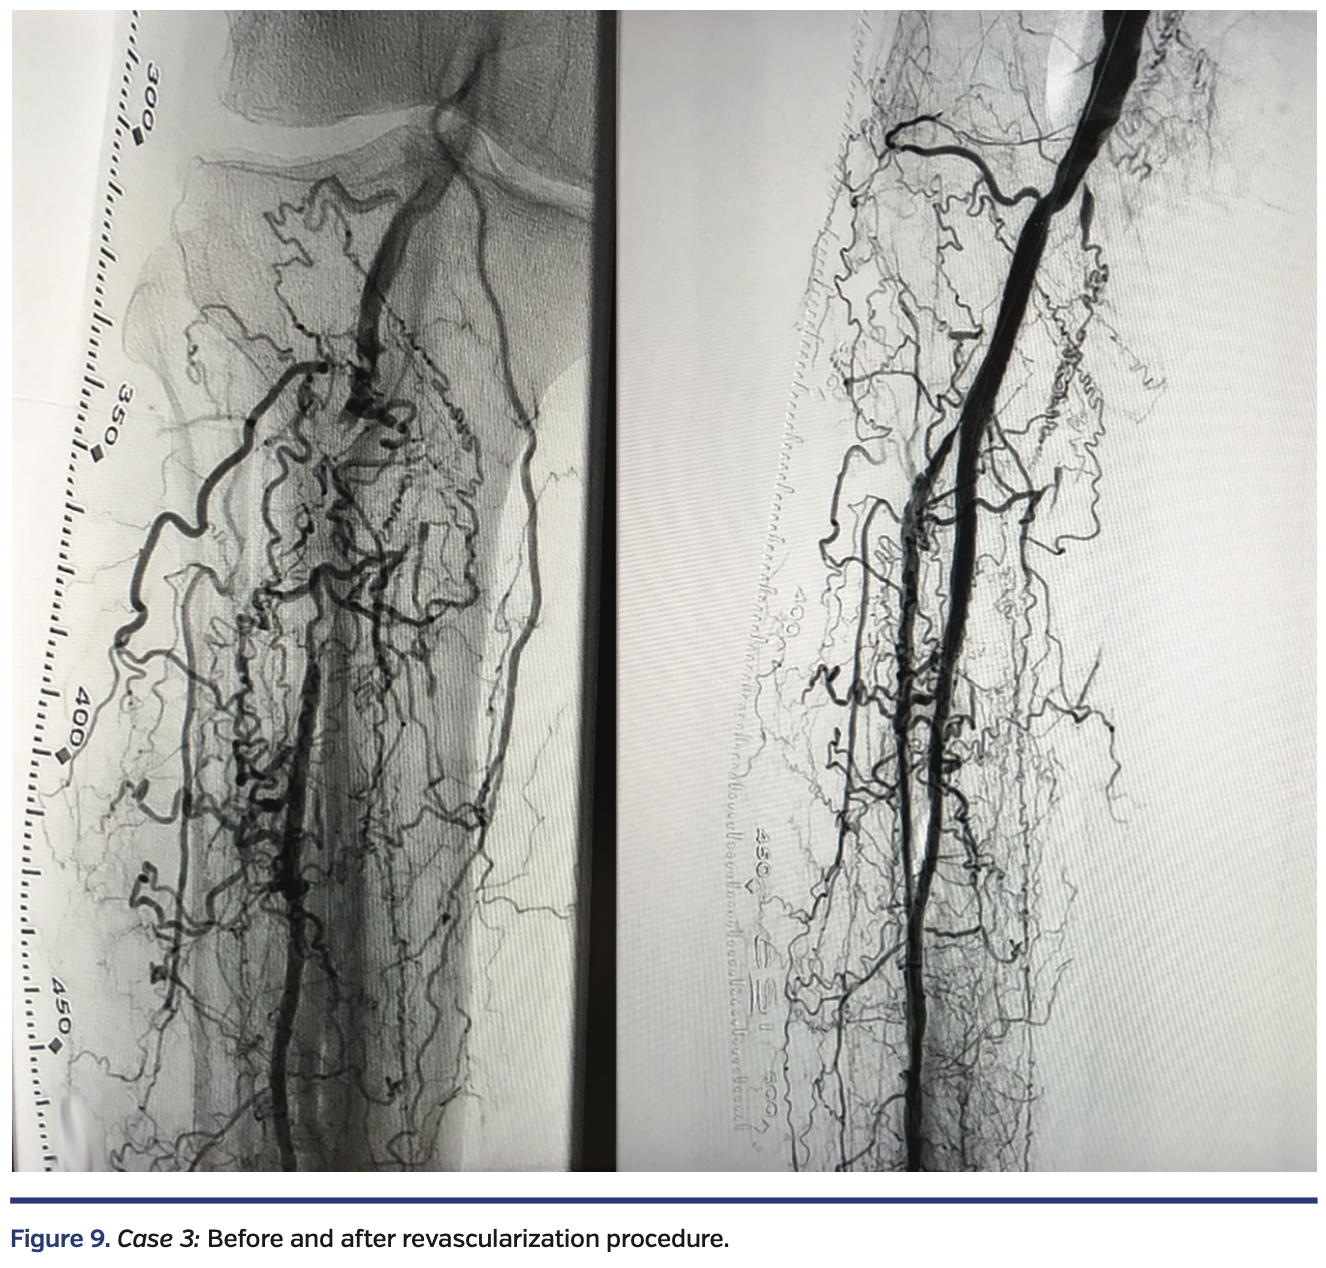

A white male in his early seventies with a history of type 2 diabetes presented with one year of claudication and a 2-month-old nonhealing ulcer at the tip of the right hallux with rest pain. Diagnostic angiography by a different physician revealed no evidence of right iliofemoral disease. The P3 segment of the right popliteal artery and the tibioperoneal trunk were occluded with recanalization of the mid peroneal artery via numerous collaterals (Figure 9, left).

A V-18 wire was advanced from the retrograde route and entered the subintimal space of the P3 segment of the popliteal artery. True lumen reentry was performed by advancing an Enteer wire with the aid of a 90 cm angled NaviCross catheter (Terumo) from the retrograde route. This wire was then exchanged out for a Fielder FC wire, followed by directional atherectomy of the right peroneal artery, right tibioperoneal trunk, and right popliteal artery, with a HawkOne M catheter advanced from the Prelude Ideal sheath, followed by balloon angioplasty with a 3.0 x 80 mm NanoCross balloon (Medtronic) and a 4.0 x 80 mm IN.PACT Admiral drug-coated balloon in the popliteal. Residual popliteal artery disease was treated with a 6 x 80 mm EverFlex self-expanding stent (Medtronic), post dilated in the proximal segment with a 6 x 40 mm and a 4 x 40 mm EverCross balloon (Medtronic) in the distal segment. To maximize blood flow and aid healing, right dorsalis pedis artery access was obtained with ultrasound and a 4 Fr merit Prelude Ideal sheath was advanced into the right distal anterior tibial artery. A knuckled Fielder FC wire was advanced into the true lumen of the right anterior tibial artery and right popliteal artery, followed by balloon angioplasty with a long 3.5 mm NanoCross balloon (Medtronic). Final angiography showed a widely patent right popliteal artery, tibioperoneal trunk, and peroneal artery (Figure 9, right). The ostium of the right anterior tibial artery was pinched, but there was normal flow in the right anterior tibial artery. There was complete resolution of the rest pain by the end of the procedure.